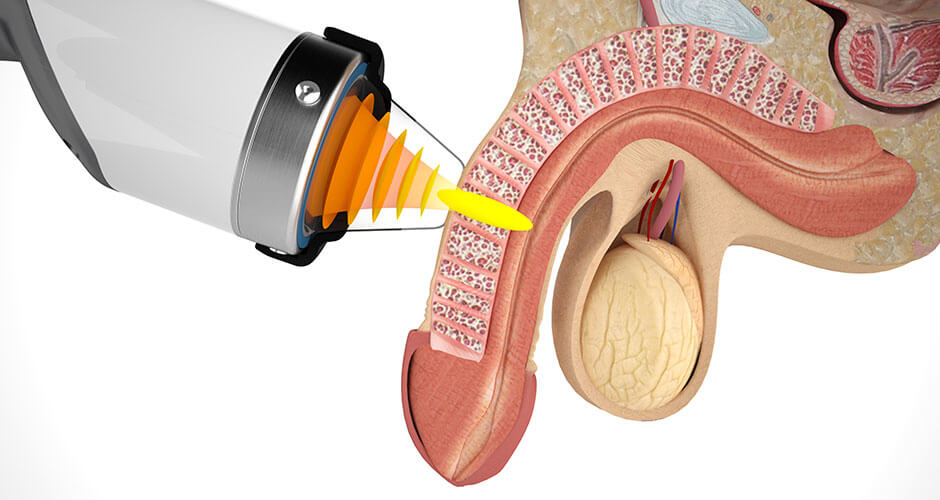

It’s a medical approach called low-intensity acoustic wave therapy.

In plain English?

Controlled sound pulses.

Micro-bursts of energy that penetrate the tissue of the penis, waking it up from the inside out.

How it works inside your body

Each gentle pulse triggers something remarkable:

New blood vessels form → increasing circulation where it matters most.

Valves strengthen → locking the blood in place, so erections stay firm.

Nerves reactivate → reconnecting the brain to the body, restoring the “signal” for desire.

Think of it like turning the power back on in a dark room.

The wiring is still there.

It just needs the right spark to flow again.